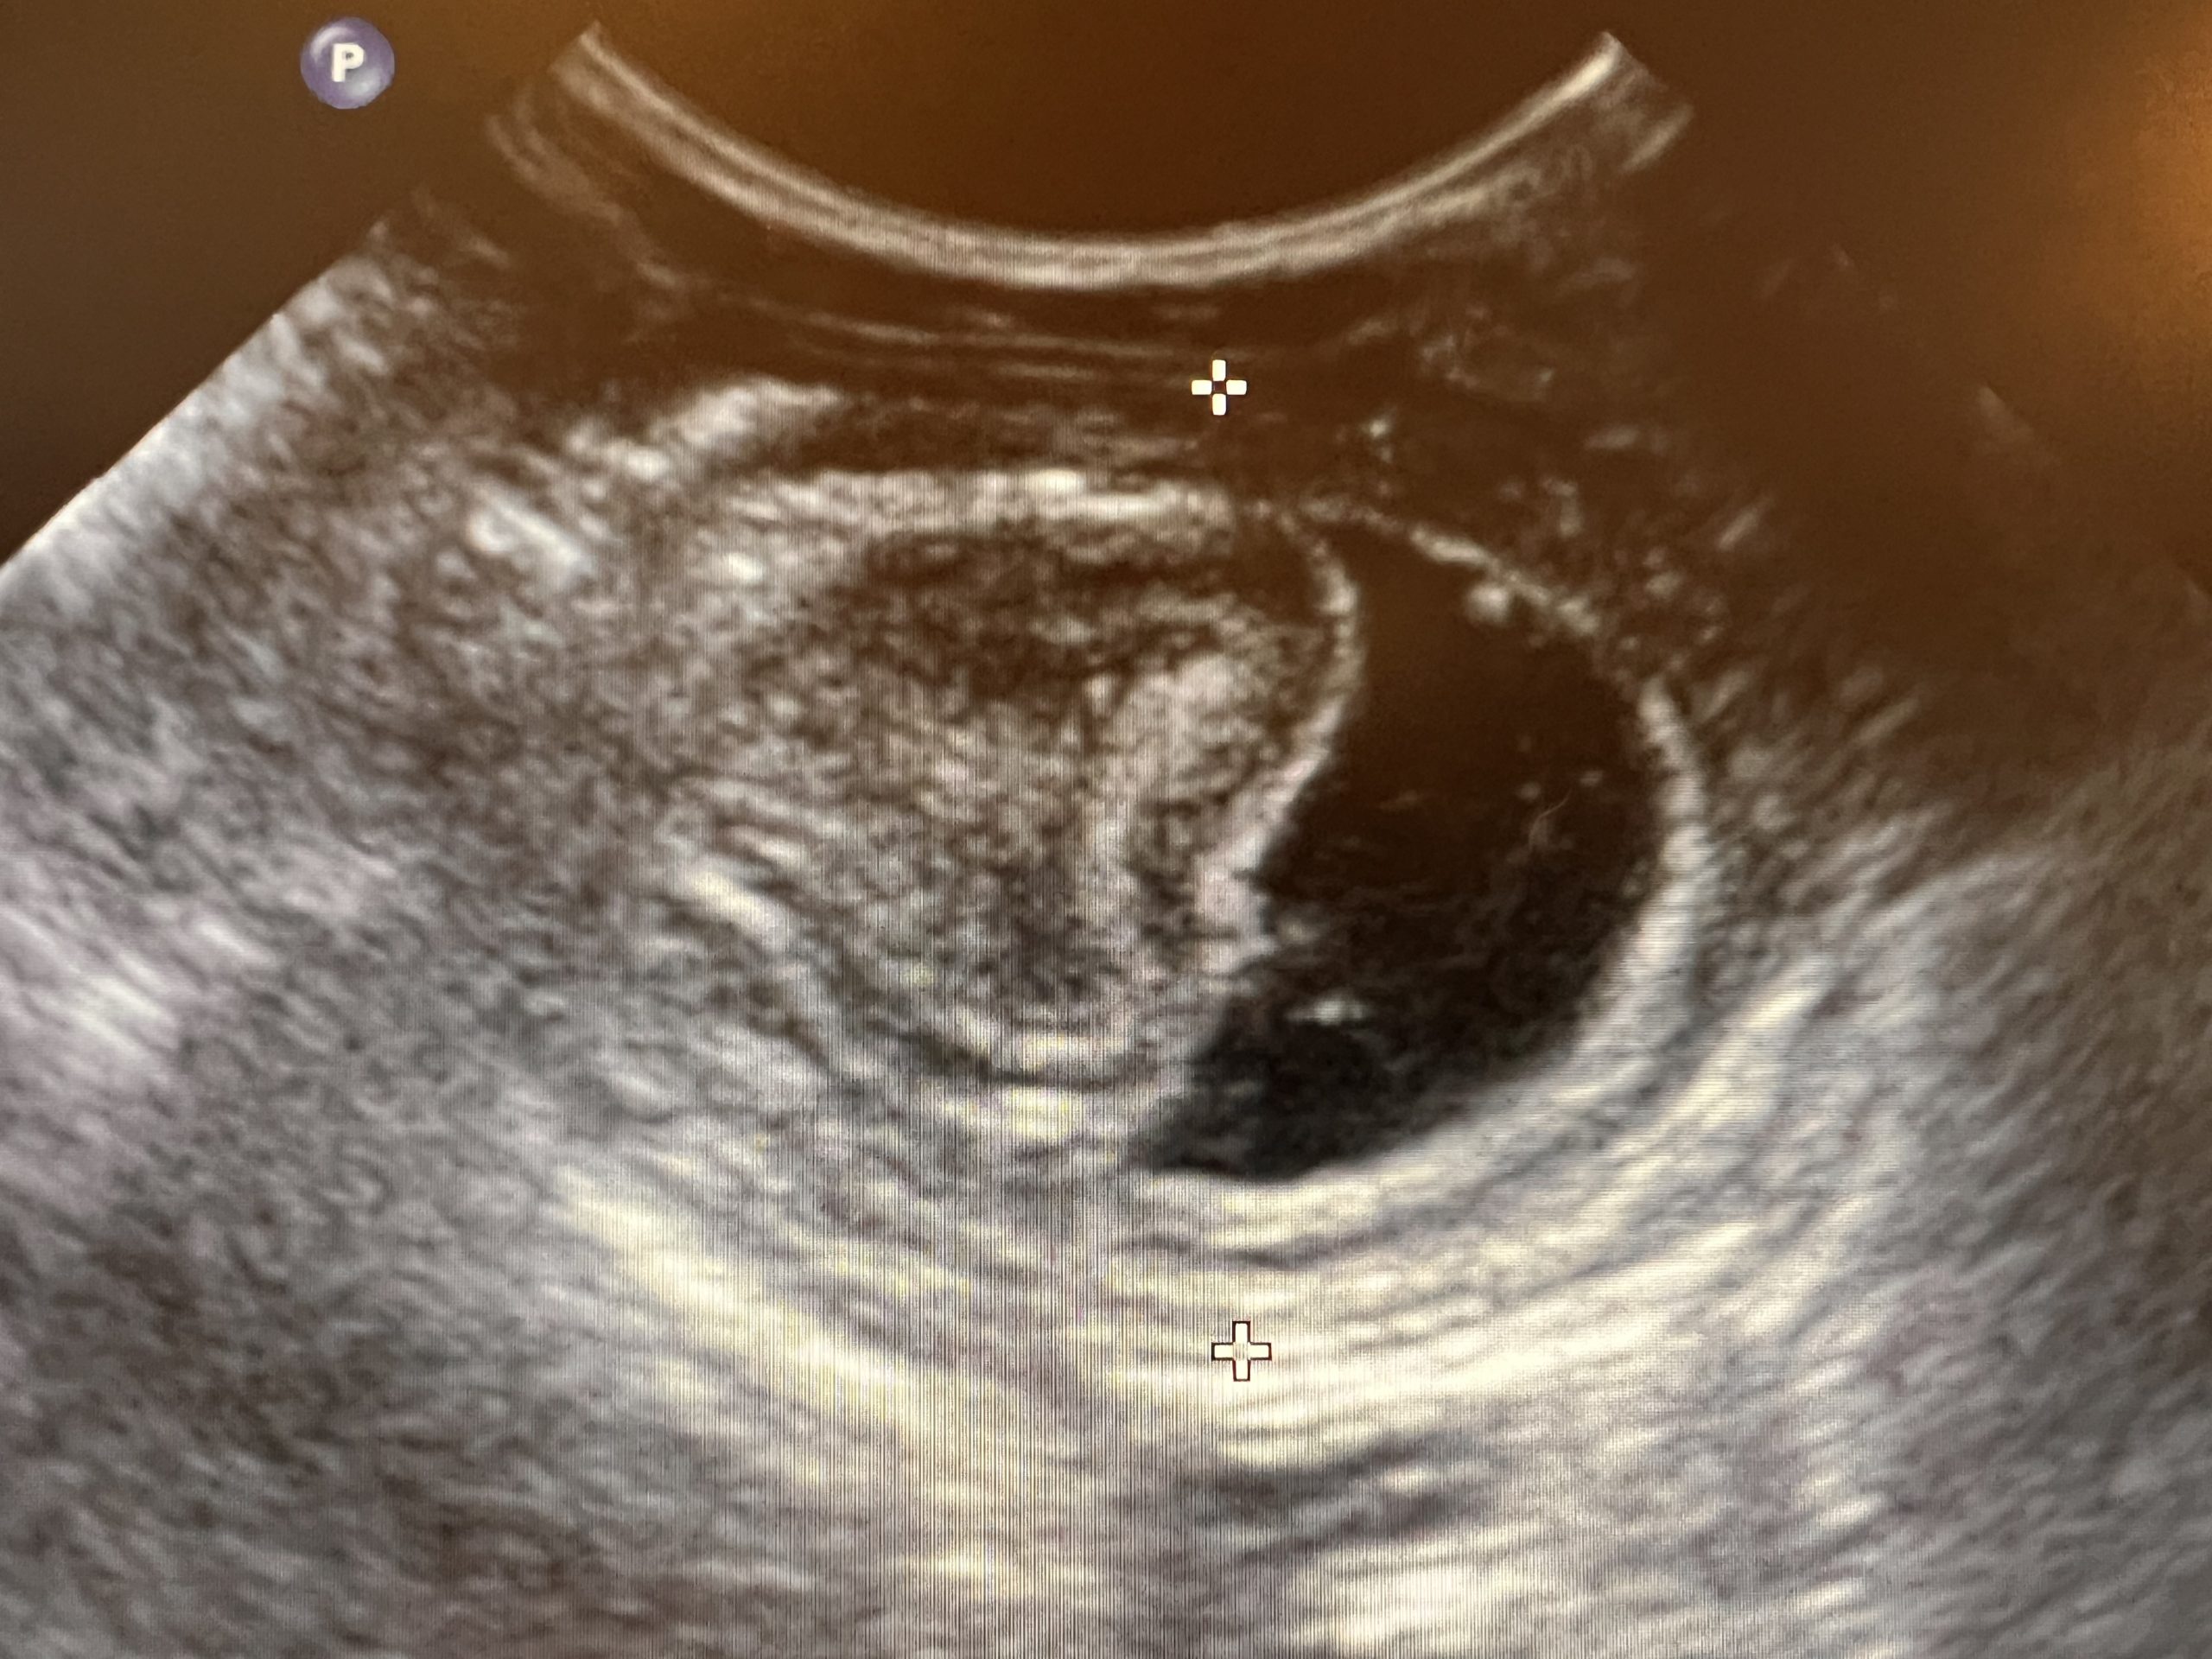

DétailsL’intussusception chez le chien et le chat: épidémiologie, diagnostic et prise en charge.

L’intussusception intestinale: qu’est-ce que c’est? L’intussusception digestive est une affection où une partie de l’intestin glisse dans une autre partie, provoquant un blocage. Cela peut affecter les chiens et les chats. Les symptômes incluent des douleurs abdominales, des vomissements, de la diarrhée sanglante, et une léthargie. C’est une urgence médicale, et un vétérinaire doit être…